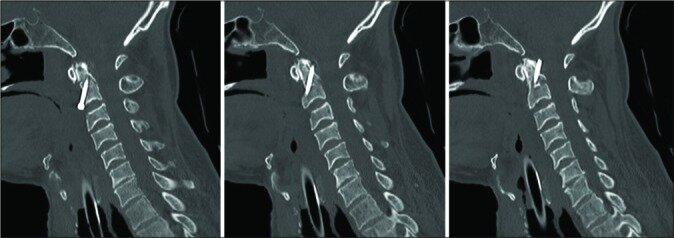

Case description: A 64-year-old neurologically intact patient with a type II odontoid fracture secondary to trauma underwent anterior odontoid screw fixation without any intraoperative complications. He tolerated the procedure well, and postoperative imaging demonstrated near anatomic correction of the fracture with satisfactory placement of the lag screw. Unfortunately, the patient was subsequently lost to follow up and he presented 7 months later for a routine outpatient computed tomography (CT) of the cervical spine, which demonstrated upward migration of the screw into the intracranial cavity abutting the medulla, with CT angiography of the neck also confirming the screw lying between the two vertebral arteries. Magnetic resonance imaging of the cervical spine also demonstrated the odontoid screw lying within close proximity to the ventral cervicomedullary junction, marginating the left vertebral artery. Subsequently, the patient was managed with removal of the odontoid screw and posterior cervical arthrodesis and instrumented fusion.